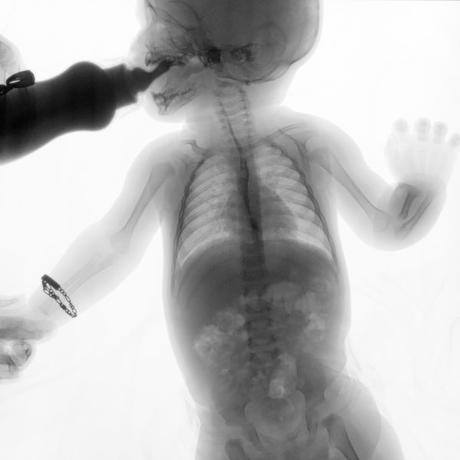

ESTUDIO SOLICITADO: SERIE ESOFAGOGASTRODUODENAL.

Se realiza Esofagograma con material de contraste baritado, por vía oral y por medio de control fluoroscópico se toman distintas proyecciones observando lo siguiente.

Se observa mecánica de la deglución con adecuado paso de medio de contraste de faringe a esófago sin presencia de defectos de llenado depósitos anómalos o fuga del mismo.

ESÓFAGO se observa de situación, calibre y trayecto normal. Contornos regulares y bien definidos. No se observan depósitos anómalos, defectos de llenado o fuga del medio de contraste.

UNION ESOFAGOGASTRICA se observa con calibre y situación normal. Sin observar reflujo a las maniobras de valsalva

ESTOMAGO se observa en su situación habitual, distendido, sin defectos de llenado.

- Actualmente no se demuestra Reflujo gastro-esofágico.

- Estudio de apariencia normal.